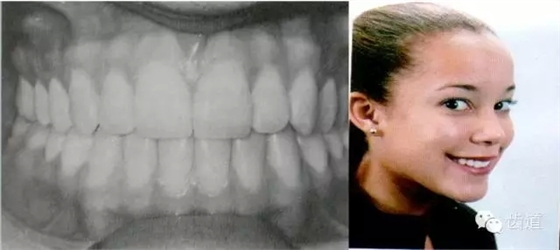

典型面形

典型面形為下頜后縮面形

典型面形為下頜前突面形